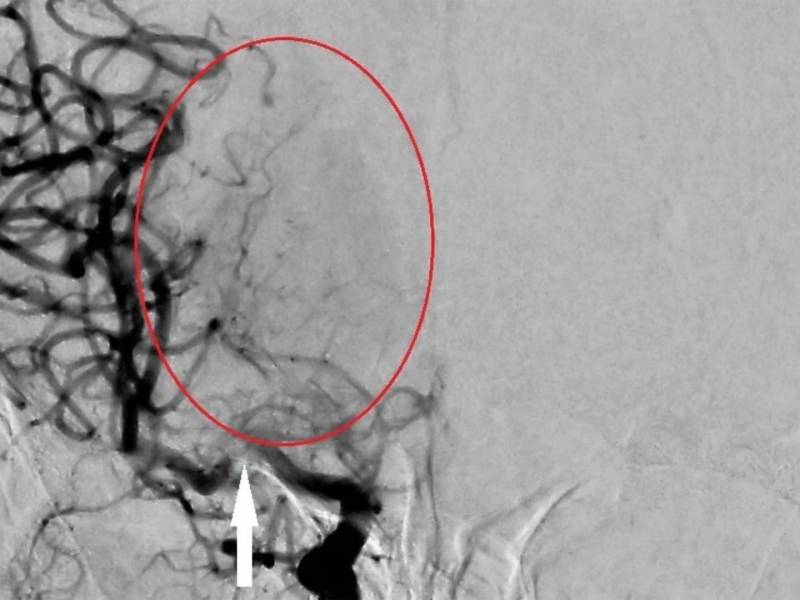

Meu nome Aridiene, tenho 21 anos . , Passei mal 12 de outubro de 2020 fui no Upa no diagnóstico deles eu não tinha nada e mesmo assim nao estava falando e nem andando mandaram eu voltar pra casa depois de 3 dias minha mãe me levou no hospital pra fazer tomografia depois de algumas horas o resultado foi*AVC ESQUEMICO HEMORRAGICO* e depois disso foi uma grande jornada fiquei internada do hospital Getúlio Vargas, o Dr. Deu um encaminhamento pra ir na secretária de saúde e foi ai que eu entrei no hospital celebro em novembro e dai diante foram várias consultas com o Neurocirurgião e Neurovascular , eles muitos atencioso pra ver meu diagnóstico, em março de 2021 fiz cateterismo foi ai o diagnóstico *MOYAMOYA , fiz uma cirurgia mais to bem melhor graças a Deus , sou muito grata por tudo Dr. Gonzalo e pela sua equipe que sempre foram atencioso e prestativo comigo ! Só tenho tenho agradecer !

Meu nome é Cristiane, e venho falar sobre o atendimento da minha filha, Thaís, portadora da doença Moyamoya. Ela precisou fazer 2 cirurgias de revascularização. O Doutor Gonzalo foi muito atencioso e simpático com minha filha e o atendimento foi top! Tudo direitinho. Obrigado a todos da equipe do Doutor Gonzalo pela a paciência com minha filha. Sei que não foi fácil!